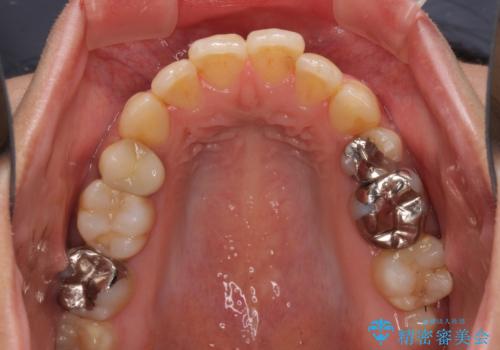

- 抜歯矯正の後戻りで前歯が突出してきていることを気にして来院された患者様です。

口元の突出感を改善するにあたり、抜歯矯正は行うことができないため、奥歯の後方移動とIPR(歯と歯の間を削る)により達成することとしました。

再度後戻りしたときに対応しやすいよう、インビザラインにて矯正治療を行うこととしました。

舌の突出癖がなかなか改善できず、IPRによる前歯の隙間が閉じきらずに、予定よりも長い治療期間となりました。